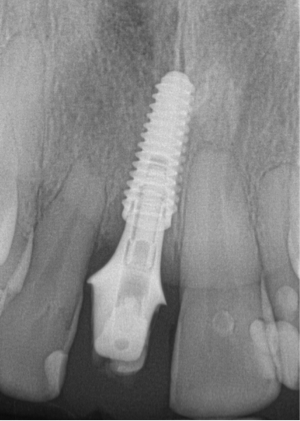

Figure 6 and Figure 7 depict a mature smile with many implant restorations. An analog impression was sent to the laboratory. The impression was scanned by the laboratory, a model was created virtually, and the implant dimensions and position were defined. The 3D surgical guide was fabricated (Figure 8), allowing the patient to receive his therapy swiftly and predictably. Tooth No. 8 was extracted, and the implant was placed and immediately loaded with an acrylic provisional treatment crown (Figure 9). The screw-retained treatment crown was fabricated in-office from a previously completed diagnostic wax-up.

After 4 months of healing and integration of the bone around the implant, the digital workflow was initiated to develop the abutment and treatment plan. Another analog impression was made with an impression post and polyvinyl impression. The laboratory scanned the impression and digitized it to create the emergence profile of the milled titanium abutment and the final restoration (Figure 10 and Figure 11). The patient had a considerably thick soft-tissue profile, allowing a milled titanium abutment. The decision to use a titanium abutment was based on the patient's occlusion and propensity to fracture teeth or restorations. The virtual model was gray because the scanner does not recognize the color of the analog impression. The virtual final abutment and crown were approved and fabrication completed. The final restoration met the patient's esthetic values and his ability to function (Figure 12 and Figure 13).

Fig 9. Surgery day with immediately loaded implant and treatment crown.

Figure 9

Fig 10. Titanium abutment proposal.

Figure 10

Fig 11. Final crown proposal.

Figure 11

Fig 12. Six months after cementation.

Figure 12

Fig 13. Radiograph 6 months after cementation.

Figure 13